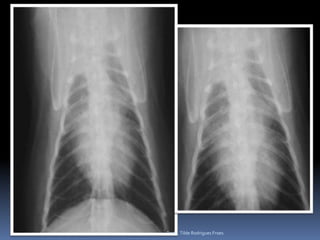

Exame radiográfico torácicoCuidados – padrões eventualmente detectados – diferenciação da sua relevânciaSilhueta cardíacaAumentos verdadeiros (posicionamento) x Gordura mediastinal – velhinhos obesosComo diferenciar (3 projeções)Gatos velhos – RX – “coração preguiçoso”Dificuldades na avaliação – escolha a Projeção VDProfa. Tilde Rodrigues Froes

Exame radiográfico torácicoCuidados – padrões eventualmente detectados – diferenciação da sua relevânciaASPECTOS RELEVANTESAumento do Átrio esquerdo (Endocardiose de mitral)Aumento generalizado (Miocardiopatia x efusão pericárdica x massa)Imagem de “D”Invertido – associado a quadros pulmonares e colapso de traquéiaProfa. Tilde Rodrigues Froes

Exame radiográfico torácicoCuidados – padrões eventualmente detectados – diferenciação de sua relevância clínicaAspecto radiográfico pulmonarPadrão intersticial  reticular difuso Fibrose senil ObesidadeMetástases (?) – pesquisa-se linfonodos associados – buscar outra técnica diagnóstica por imagemPadrão intersticial nodular (focal o multifocal)Pequenos nódulos – vasos em cortes transversaisOutros diferenciais: degeneração costo-condral, massa externa – mamaria.Pequenos nódulos – 2-4mm – OSTEOMASUsualmente visualizados em animais de grande porte Diferenciar de MetástasesProfa. Tilde Rodrigues Froes

Exame radiográfico torácicoPesquisa de metástasesDiferentes padrõesIntersticial reticularIntersticial reticulonodularIntersticial nodularAlveolar (quando ?)Áreas cavitárias* Considerar sempre as limitações dessa análise* Em gatos* Efusão pleuralProfa. Tilde Rodrigues Froes